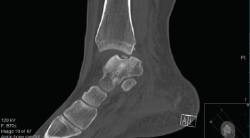

Otras clasificaciones están basadas en la tomografía axial computarizada (TAC) o en la resonancia magnética (RM) y engloban las LOC tanto agudas como crónicas. El estudio mediante TAC permite más precisión para definir el tamaño y la localización de las lesiones, así como de la presencia de cambios quísticos. Ferkel y Sgaglione desarrollaron un sistema de clasificación basado en la TAC (Figura 2), que tiene la particularidad de servir de apoyo para la planificación preoperatoria y la elección del tipo de tratamiento más adecuado (tornillo/pin, microfractura o injerto)(18).

Figura 3. Imagen de tomografía axial computarizada de un estadio III que muestra un fragmento no desplazado con lucencia por debajo.

Tanto la TAC como la RM son más sensibles y han demostrado una precisión similar cuando se emplea la TAC helicoidal de alta resolución(25). La RM puede delinear mejor el cartílago y distinguir entre cartílago nativo y reparativo (fibrocartílago); también puede valorar mejor los cambios del tejido sinovial(26). Además, la secuencia de mapeo T2 de RM puede proporcionar información suplementaria sobre la matriz del tejido reparador(27,28). Otra de las ventajas de la RM frete a la TAC la constituye la visualización de la patología concomitante de los tejidos blandos. Sin embargo, presenta una desventaja al evaluar el edema óseo circundante, lo que tiende a sobrestimar el tamaño de la lesión, especialmente porque el tamaño de la lesión dicta el tipo de tratamiento y el pronóstico, haciendo necesario evaluar con precisión el tamaño cuando se propone el tratamiento(29,30).

Una TAC helicoidal ayudará preferiblemente en la planificación preoperatoria, ya que permite caracterizar mejor el tamaño de la lesión, su ubicación y el grado de desplazamiento(31). Eso sí, a expensas de una mayor exposición a la radiación.